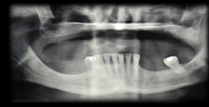

Al presente taller le correspondió evaluar la zona posterior maxilar. El maxilar posterior tiene naturalmente baja altura del proceso alveolar, anatómicamente limitada por el seno maxilar. Las raíces de los molares están muy relacionadas con el piso del seno maxilar. En el centro de la cresta alveolar, se encuentra la región de trifurcación radicular, sitio ideal desde punto de vista protético para la instalación del implante, y donde se encuentra la menor altura de hueso del piso del seno. Lo mencionado hace, que la instalación de implantes de dimensiones estándar después de la pérdida de dientes en ésta región, sea limitada. Los procesos de resorción resultantes de dicha pérdida, común a todas las regiones del proceso alveolar pueden agravar esta situación. La neumatización del seno maxilar, debido al aumento de la actividad osteoclástica a lo largo de la membrana sinusal y la ausencia de la ”barrera” dentaria a los cambios de presiones aéreas sinusales puede afectar la morfología de este sitio. Estas condiciones determinan un desafío anatómico para el tratamiento del maxilar edéntulo posterior utilizando implantes dentales. Las técnicas de reconstrucción de los defectos del reborde alveolar residual con procedimientos de injerto de hueso autógeno tienen resultados predecibles, que se describen en la literatura. Una explicación de sus buenos resultados es el hecho de no tener reacciones inmunes que puedan interferir con el proceso de remodelación y desarrollo del tejido. Tienen intrínsecamente a los osteoblastos y los factores de crecimiento responsables de los cambios celulares que se producen después de la implantación y que culminan en la remodelación y la formación de hueso en ese sitio1. Su desventaja, es la necesidad de un área quirúrgica adicional donante que puede ser de ubicación intraoral, en los casos en que la necesidad de reconstrucción sea pequeña, o extraoral en los casos de medianas o grandes reconstrucciones. En la década de 1980, se han descrito técnicas de injerto de hueso en el seno maxilar con el fin de resolver el problema de la falta de hueso y permitir la colocación del implante. Una de las técnicas descriptas es la cirugía para levantar el suelo del seno maxilar, conocido por su nombre en inglés - Sinus Lift2,3.

Diversas alternativas a la técnica y diferentes tipos de injertos y biomateriales de diferentes naturaleza se han propuesto como una alternativa al uso de hueso autógeno para llenar la cavidad resultante de la elevación del piso del seno. El suministro limitado del hueso autógeno en relación con el volumen necesario para la elevación de seno, así como la facilidad en su uso y técnica con un muy buen rendimiento clínico, animó a la aplicación de biomateriales. Philip Boyne2 (1983) describe la reconstrucción de fracturas con hueso bovino. Sus estudios eran parte del desarrollo de hueso bovino inorgánico, material con alta similitud al hueso humano. Estudios en animales sugieren que el hueso bovino desproteinizado es reabsorbido y sustituido gradualmente por tejido óseo viable. Es un proceso lento comparándolo con autoinjertos4, lo que permite la conservación de la macroestructura reconstruida durante todo el proceso de sustitución. Dependiendo de la disponibilidad ósea (en altura y ancho) en la zona maxilar posterior las opciones para colocar implantes en el lugar correcto son: